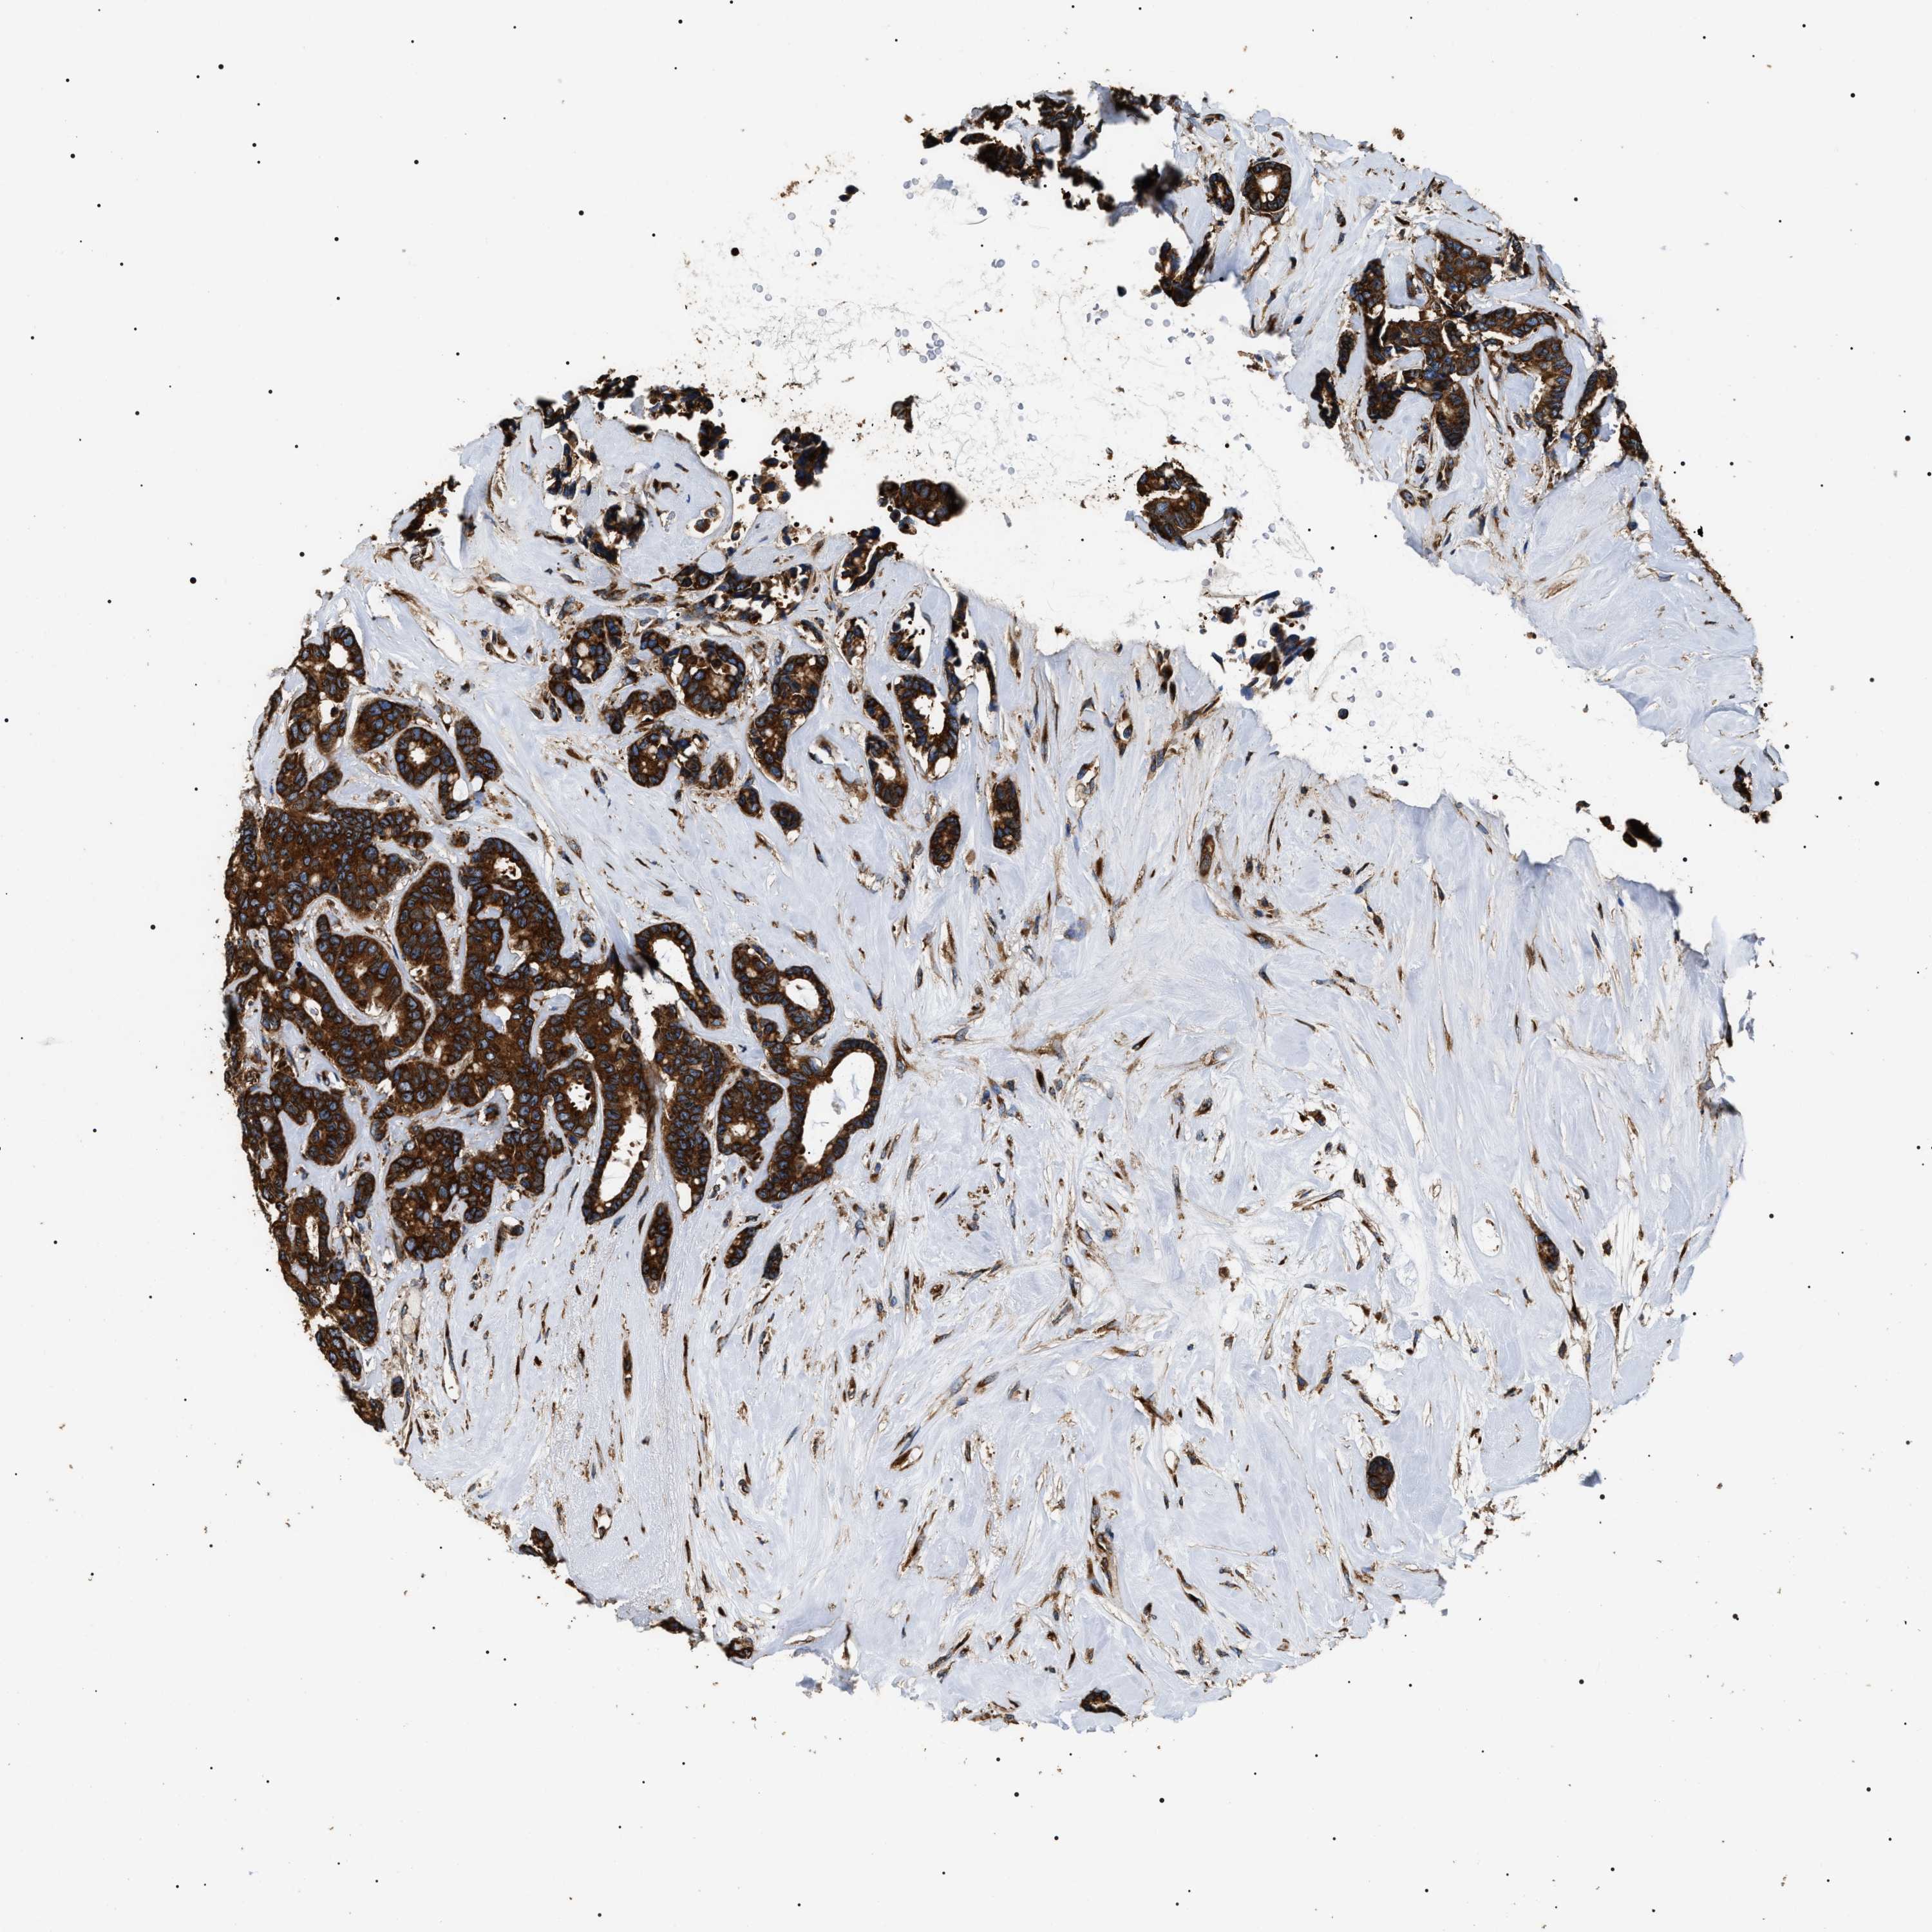

CANCER BREAST CANCER Show tissue menu

BRCA TCGA BRCA VALIDATION PROTEIN EXPRESSION